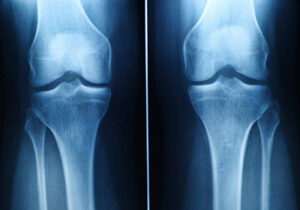

Dr. Satvir treated my grandmother for knees replacement surgery jn december. He was very thorough and explained everything to us and clear all our doubts in concise manner. He is an excellent surgery. We were very happy with his treatment.